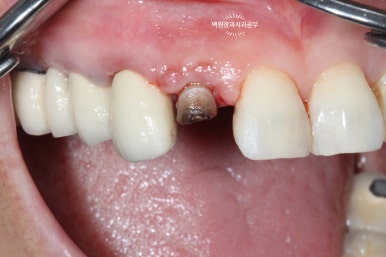

약 10일 정도 지나면, 봉합사를 제거합니다.

치아가 아직 흔들흔들 합니다.

약 10일 정도 지나면 실밥을 제거 할 수 있어요. 저희는 봉합사 제거라고 부릅니다. ㅎㅎㅎ

10일 정도 지나면 아직 치아가 흔들흔들 하긴 합니다.

약 한달 정도는 기다리셔야 합니다.

기다리는 동안 임시치아 만들어 드립니다.

앞니니깐 일단 급한대로 임시치아를 만들어 드렸습니다.

앞에서 보았을 때 어느정도 커버만 되면 되기 때문에, 보시다시피 얇은 레진치아를 사용하여 양 옆에 붙여드렸어요.

그래도 생각보단 자연스러워서 한달 정도 조심히 쓰시면 충분히 괜찮습니다.